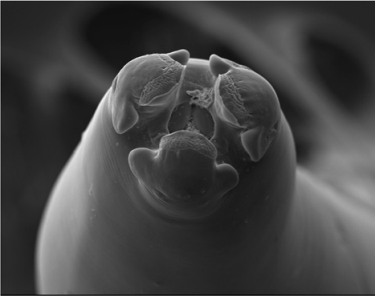

As técnicas de microscopia evoluíram muito desde as primeiras análises de estruturas biológicas realizadas pelo inglês Robert Hooke e pelo holandês Anton Van Leeuwenhoek, no século XVII.

Figura I

Figura II

Figura III

Considerando-se as três figuras precedentes, selecione a opção que apresenta, respectivamente, a modalidade de microscopia empregada na obtenção de cada uma delas.